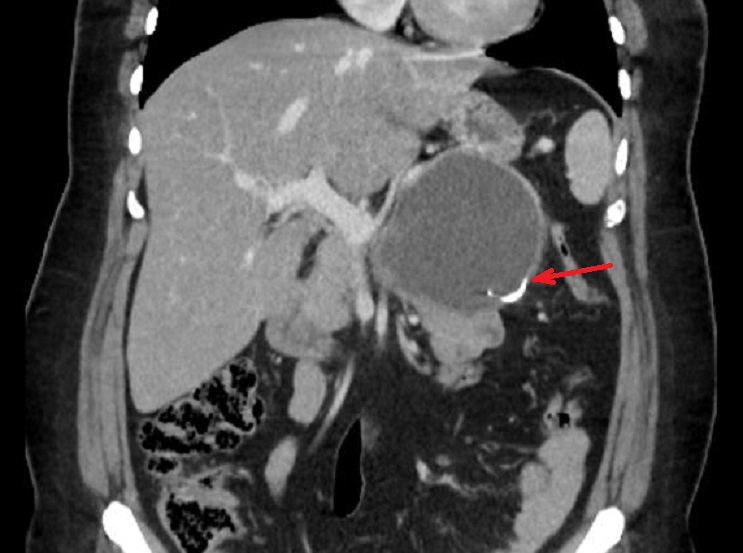

Image radiologique TDM d'une

cystadenome sereux multikystique cephalique du

pancreas a aspect multikystique comporte de plusieur

kyste hypodensite de < 2cm situe a la tete du

pancreas ( fleche rouge ) . Coupe TDM axcilaire |